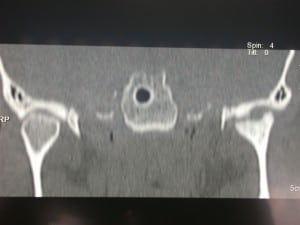

Artrosi dell’Articolazione Temporo-Mandibolare

L’artrosi o osteoartrosi (OA) rappresenta l’artropatia più comune dell’articolazione temporo – mandibolare (ATM).

Come per le altre localizzazioni , anche l’OA dell’ATM (Artrosi dell’Articolazione Temporo-Mandibolare) riconosce una patogenesi multifattoriale, caratterizzata dalla degenerazione progressiva della cartilagine articolare e da alterazioni dell’osso subcondrale.

La sintomatologia è frequentemente caratterizzata da dolorabilità alla palpazione, rumori articolari, in particolare crepitii, riduzione della motilità mandibolare e dolore nell’esecuzione dei normali movimenti.